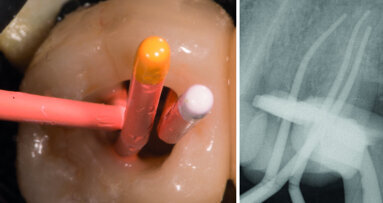

Ces dents sont un réel défi à restaurer, lorsque l’élimination de l’ancien matériau de restauration et de la carie, conduit à la nécessité de remplacer des quantités considérables de structure dentaire (Fig. 11). Ces dents requièrent la mise en place de tenons pour maintenir le moignon coronaire de la structure dentaire résiduelle.

Étant donné que la finalité des tenons est de maintenir le moignon, il est recommandé de placer un tenon dans chacun des canaux de dents multi-canalaires, afin de fixer le moignon coronaire de part en part de la structure dentaire résiduelle (Fig. 12). Si l’on observe la projection des tenons dans les dents postérieures, on remarque que l’angulation des canaux mène à une convergence des tenons dans la partie coronaire de la dent. Ceci bloque le moignon coronaire et contribue à prévenir une fracture du tenon ou son délogement, lors de la fonction masticatoire, ce que l’on peut observer lors de la pose d’un seul tenon.